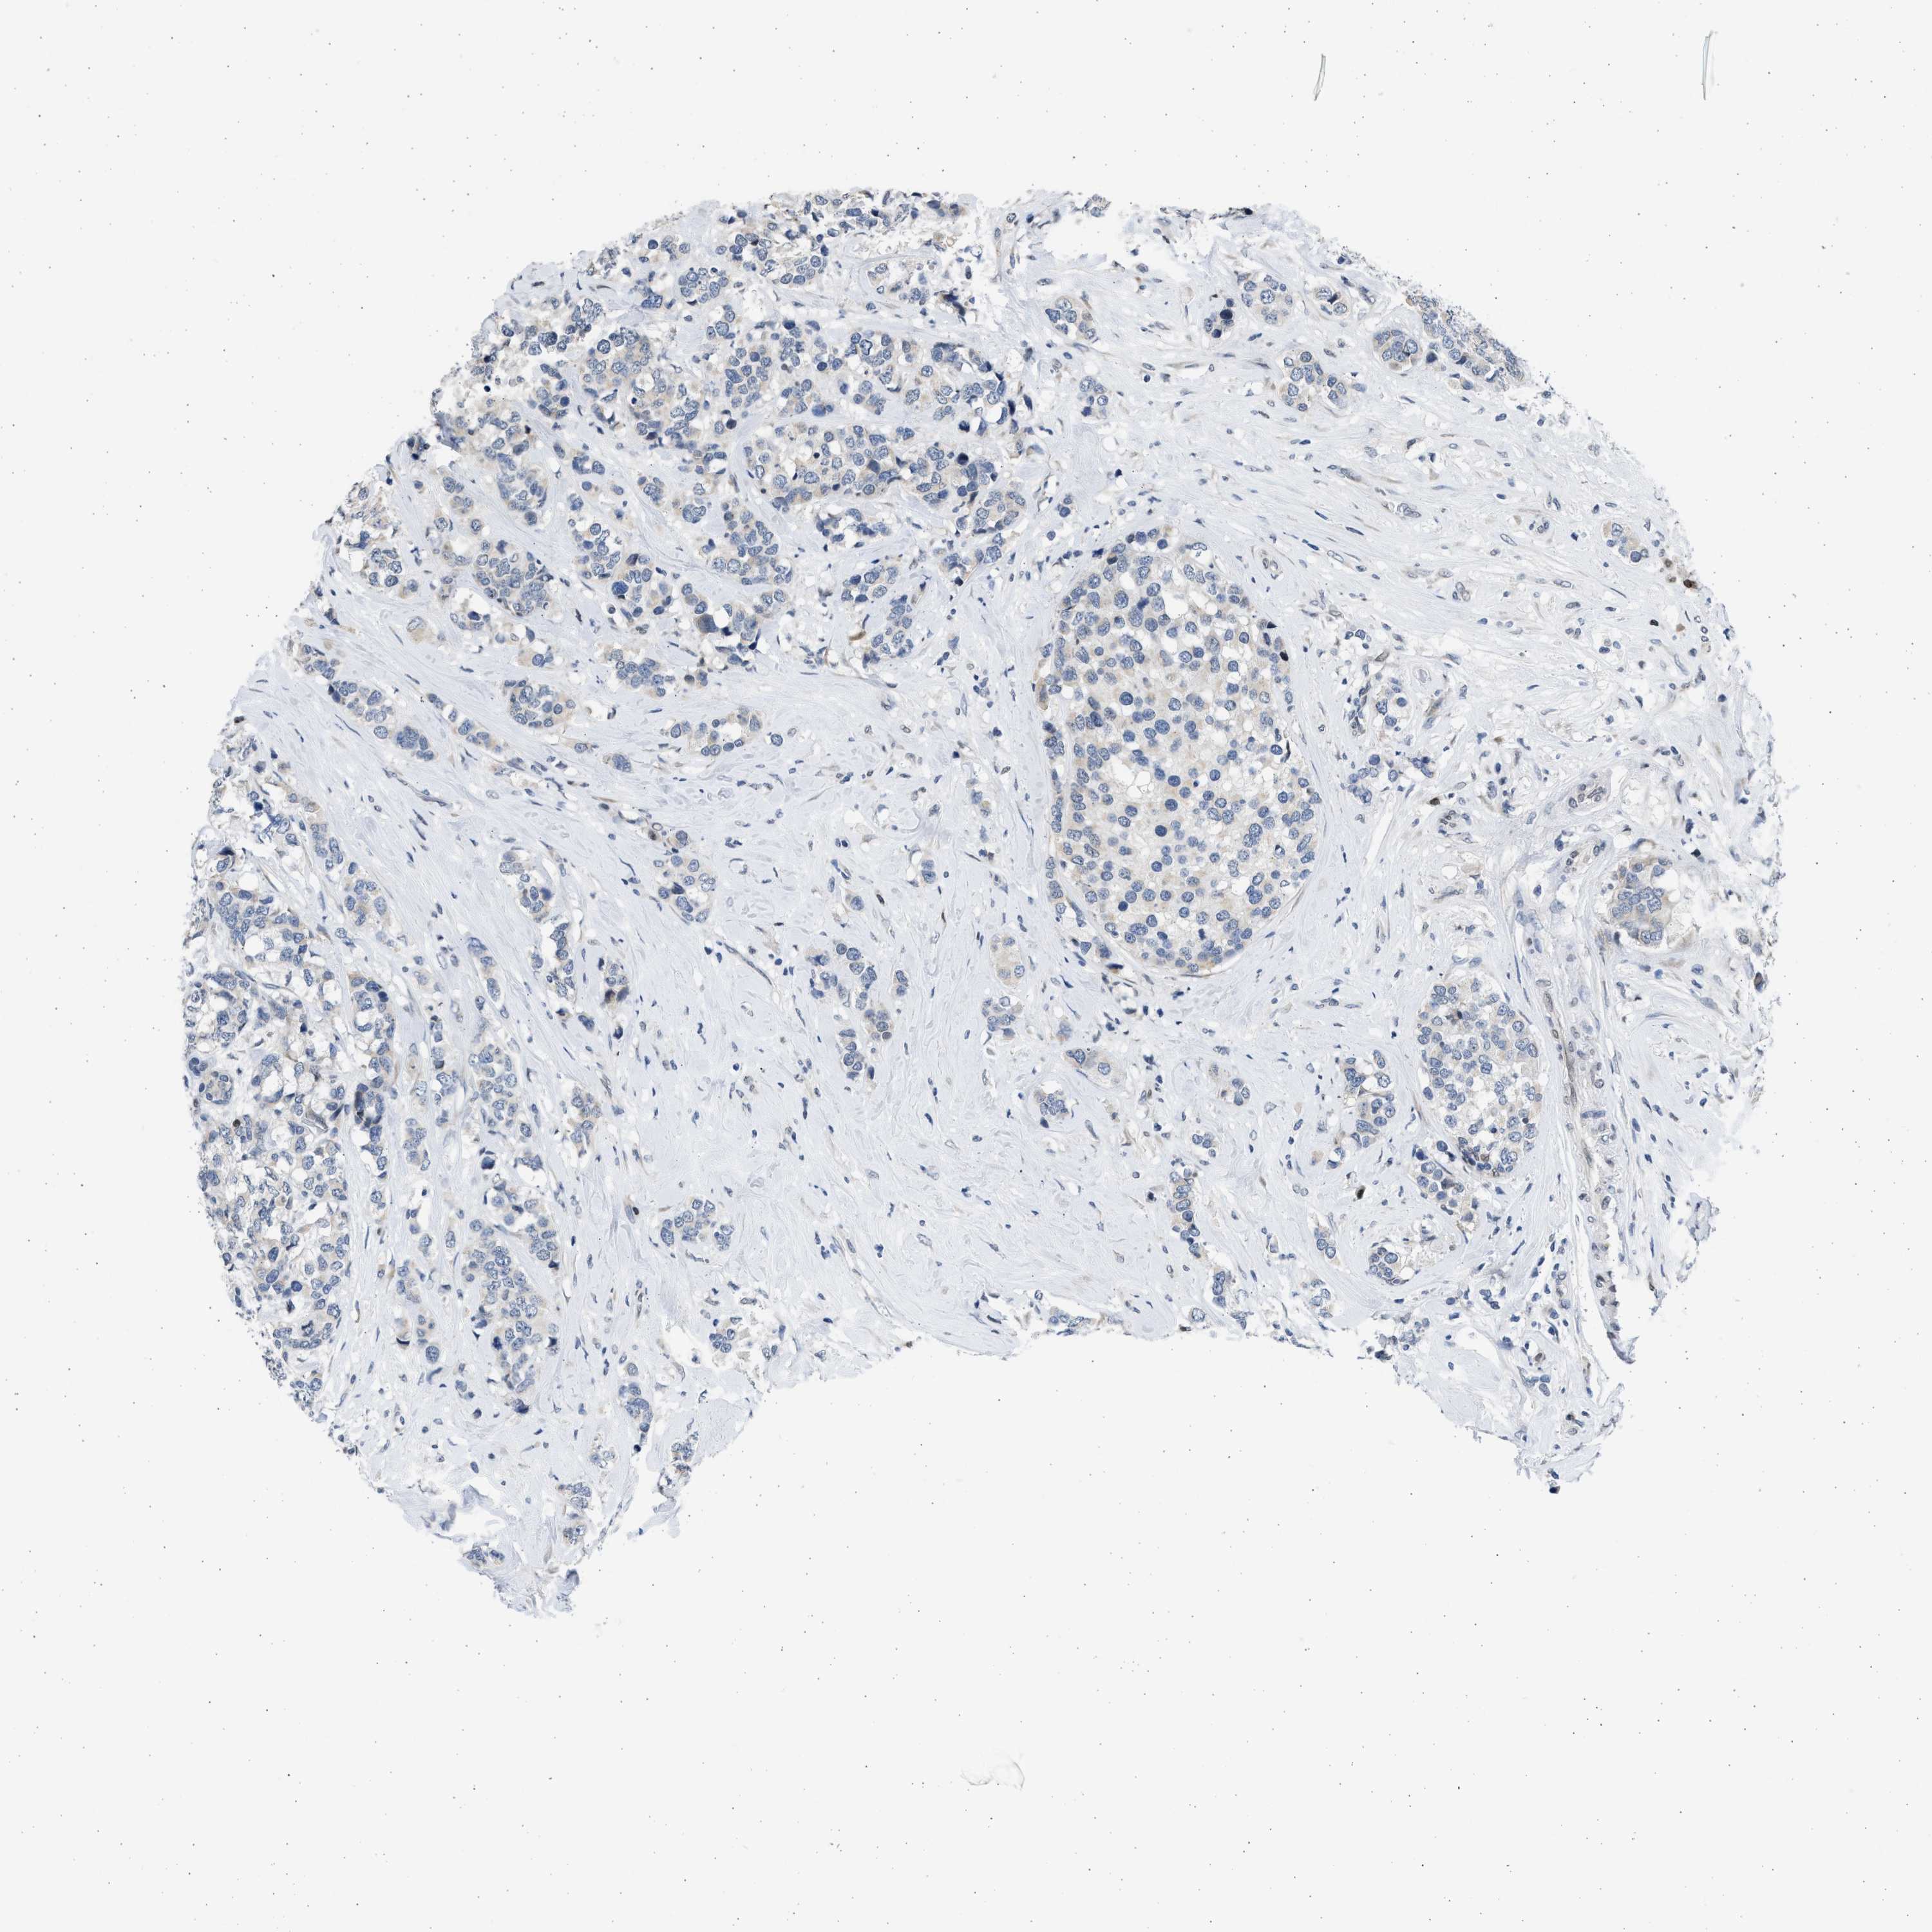

CANCER BREAST CANCER Show tissue menu

BRCA TCGA BRCA VALIDATION PROTEIN EXPRESSION

ANTIBODIES

AND

VALIDATION